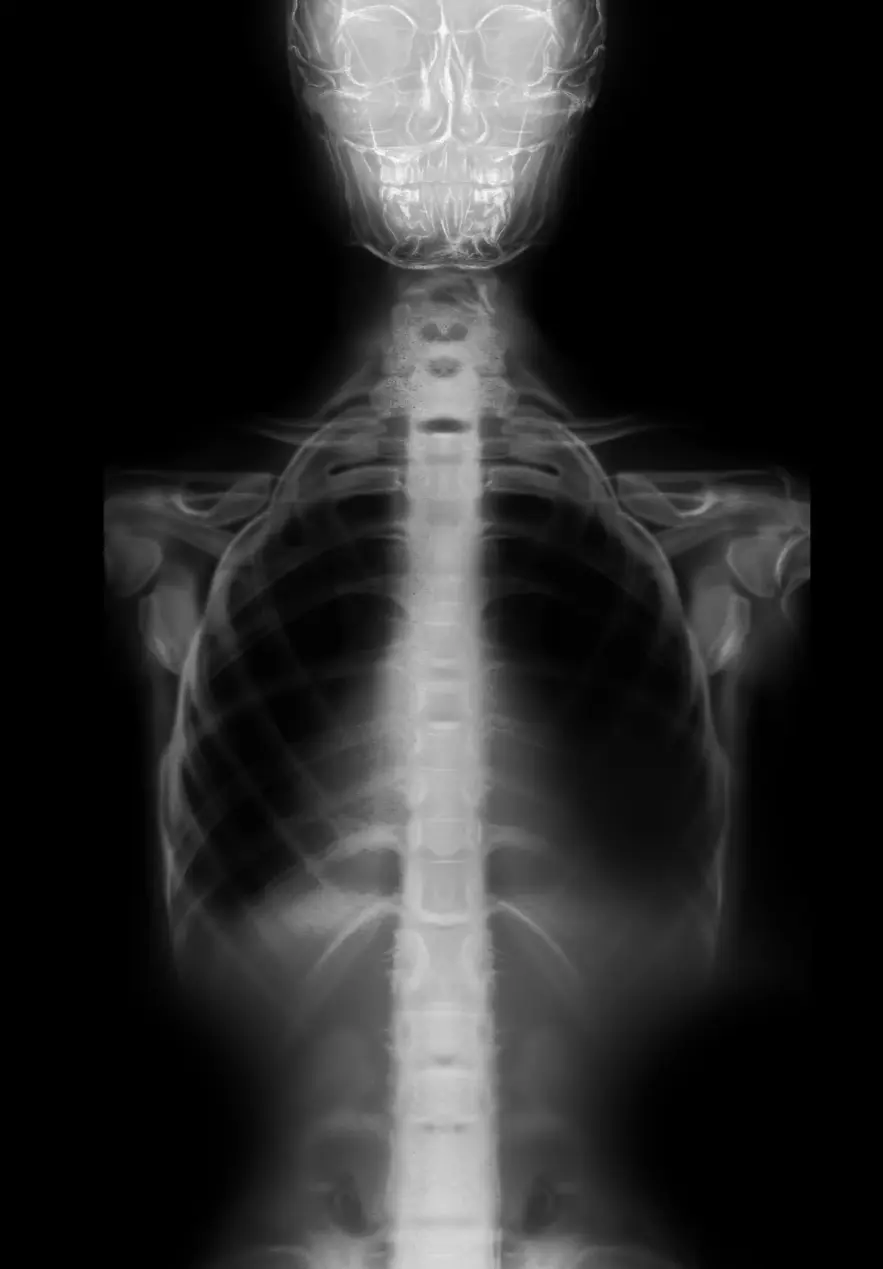

Después